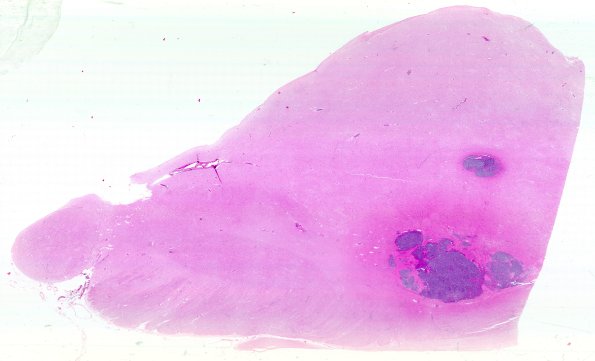

Multiple hemorrhages appreciated grossly in cerebral cortex and brainstem prove on microscopic examination to consist of a rim of fresh hemorrhage surrounding a pure collection of white cells most of which appear to be myeloblasts. These lesions have a predilection for the area of the grey-white junction